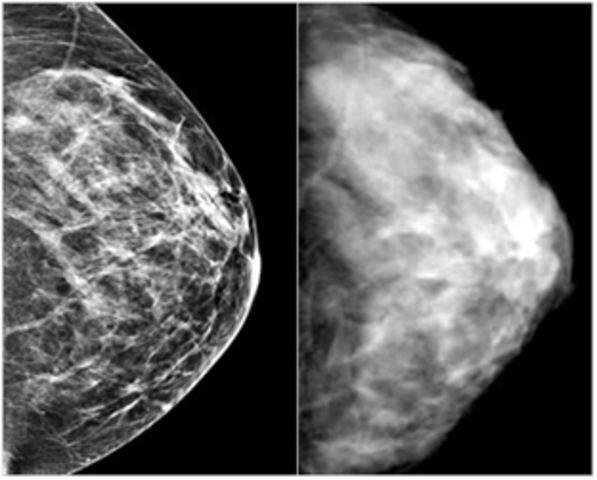

Growing use of Mamography saves lives, helping to detect cancers at an early stage